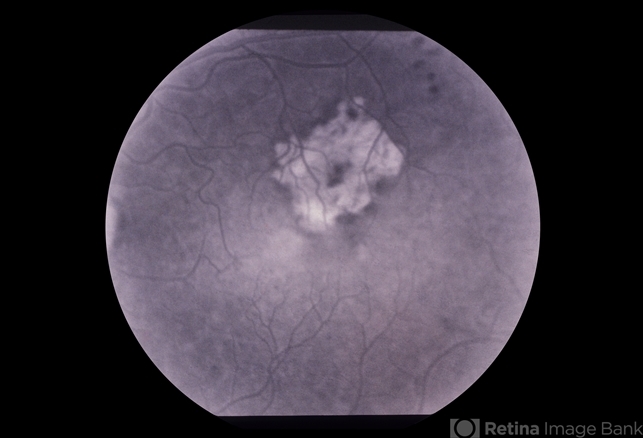

- ARMD Laser Rx

- wet age-related macular degeneration (wet AMD)